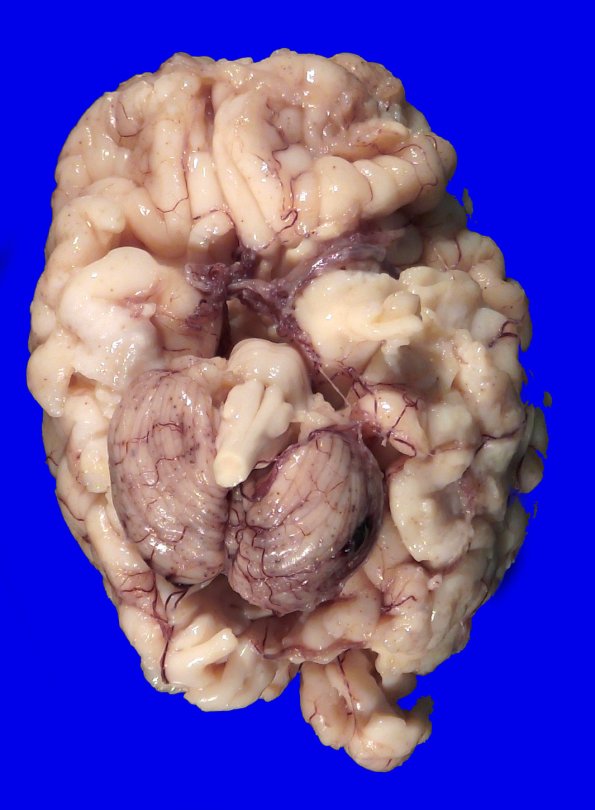

4A1,2 At autopsy the unfixed brain weighed 415g (normal: 356 +/- 79g). The gross appearance of the brain is fairly normal, although the cerebellar hemispheres appear somewhat atrophic.